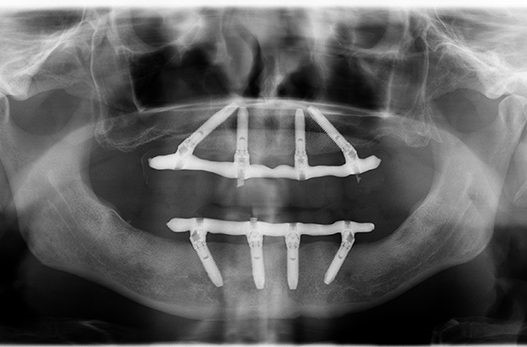

При технологии «всё на 4» устанавливается четыре основных импланта: два в проекции вторых зубов, и ещё два — под углом, чтобы шахта импланта вышла под пятым и шестым зубом. И эти четыре атланта держат весь челюстной протез. Выглядит это так:

Протезирование верхней и нижней челюстей на четырёх имплантах